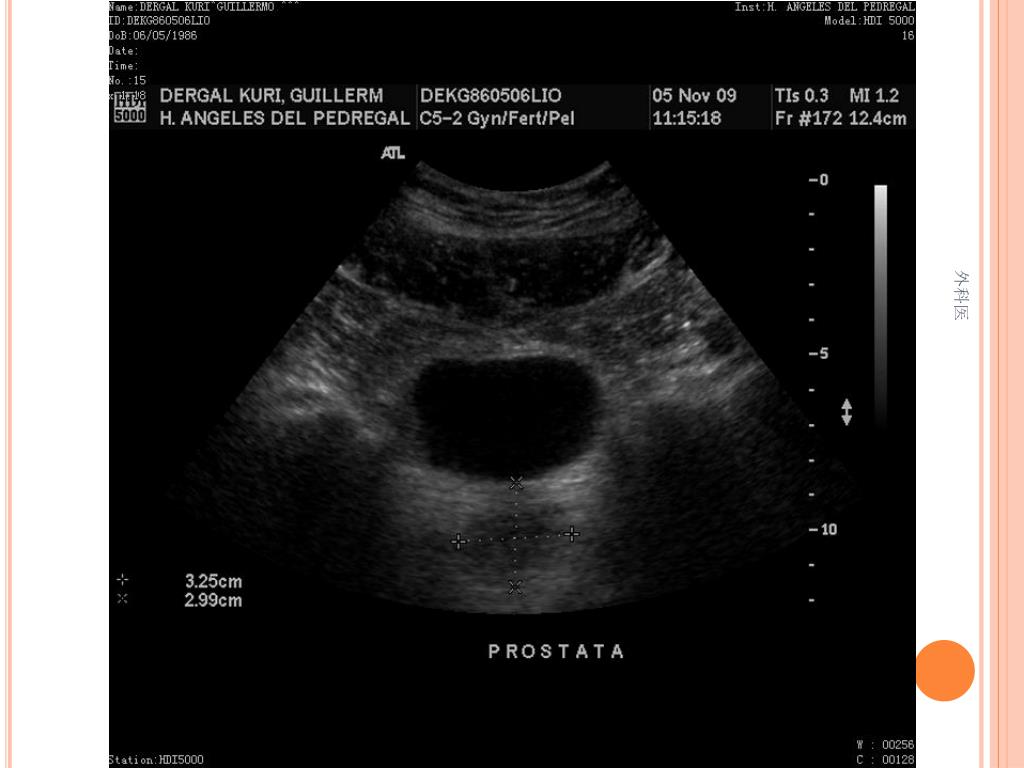

36. PATOLOGIA 外科医

41. PRODUCTO DE RESECCION INTESTINAL: APENDICITIS AGUDA FIBRINOPURULENTA, FIBROSIS PERIAPENDICULAR SEVERA. ILEON TERMINAL Y COLON CON HIPERPLASIA LINFOIDE FOLICULAR Y PERITONITIS AGUDA 外科医